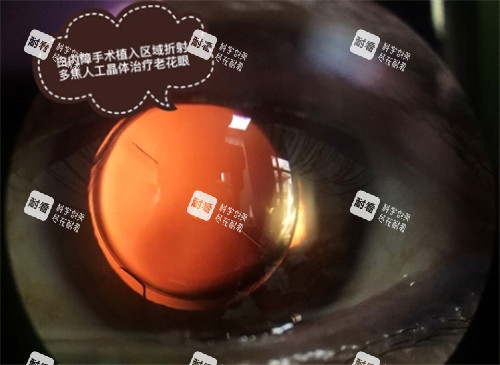

田蔓男 白内障、三焦点晶体植入 周三全天+周五上午 “78岁,白内障手术15分钟做完,现在看远看近都清楚,不用戴老花镜”(李爷爷)